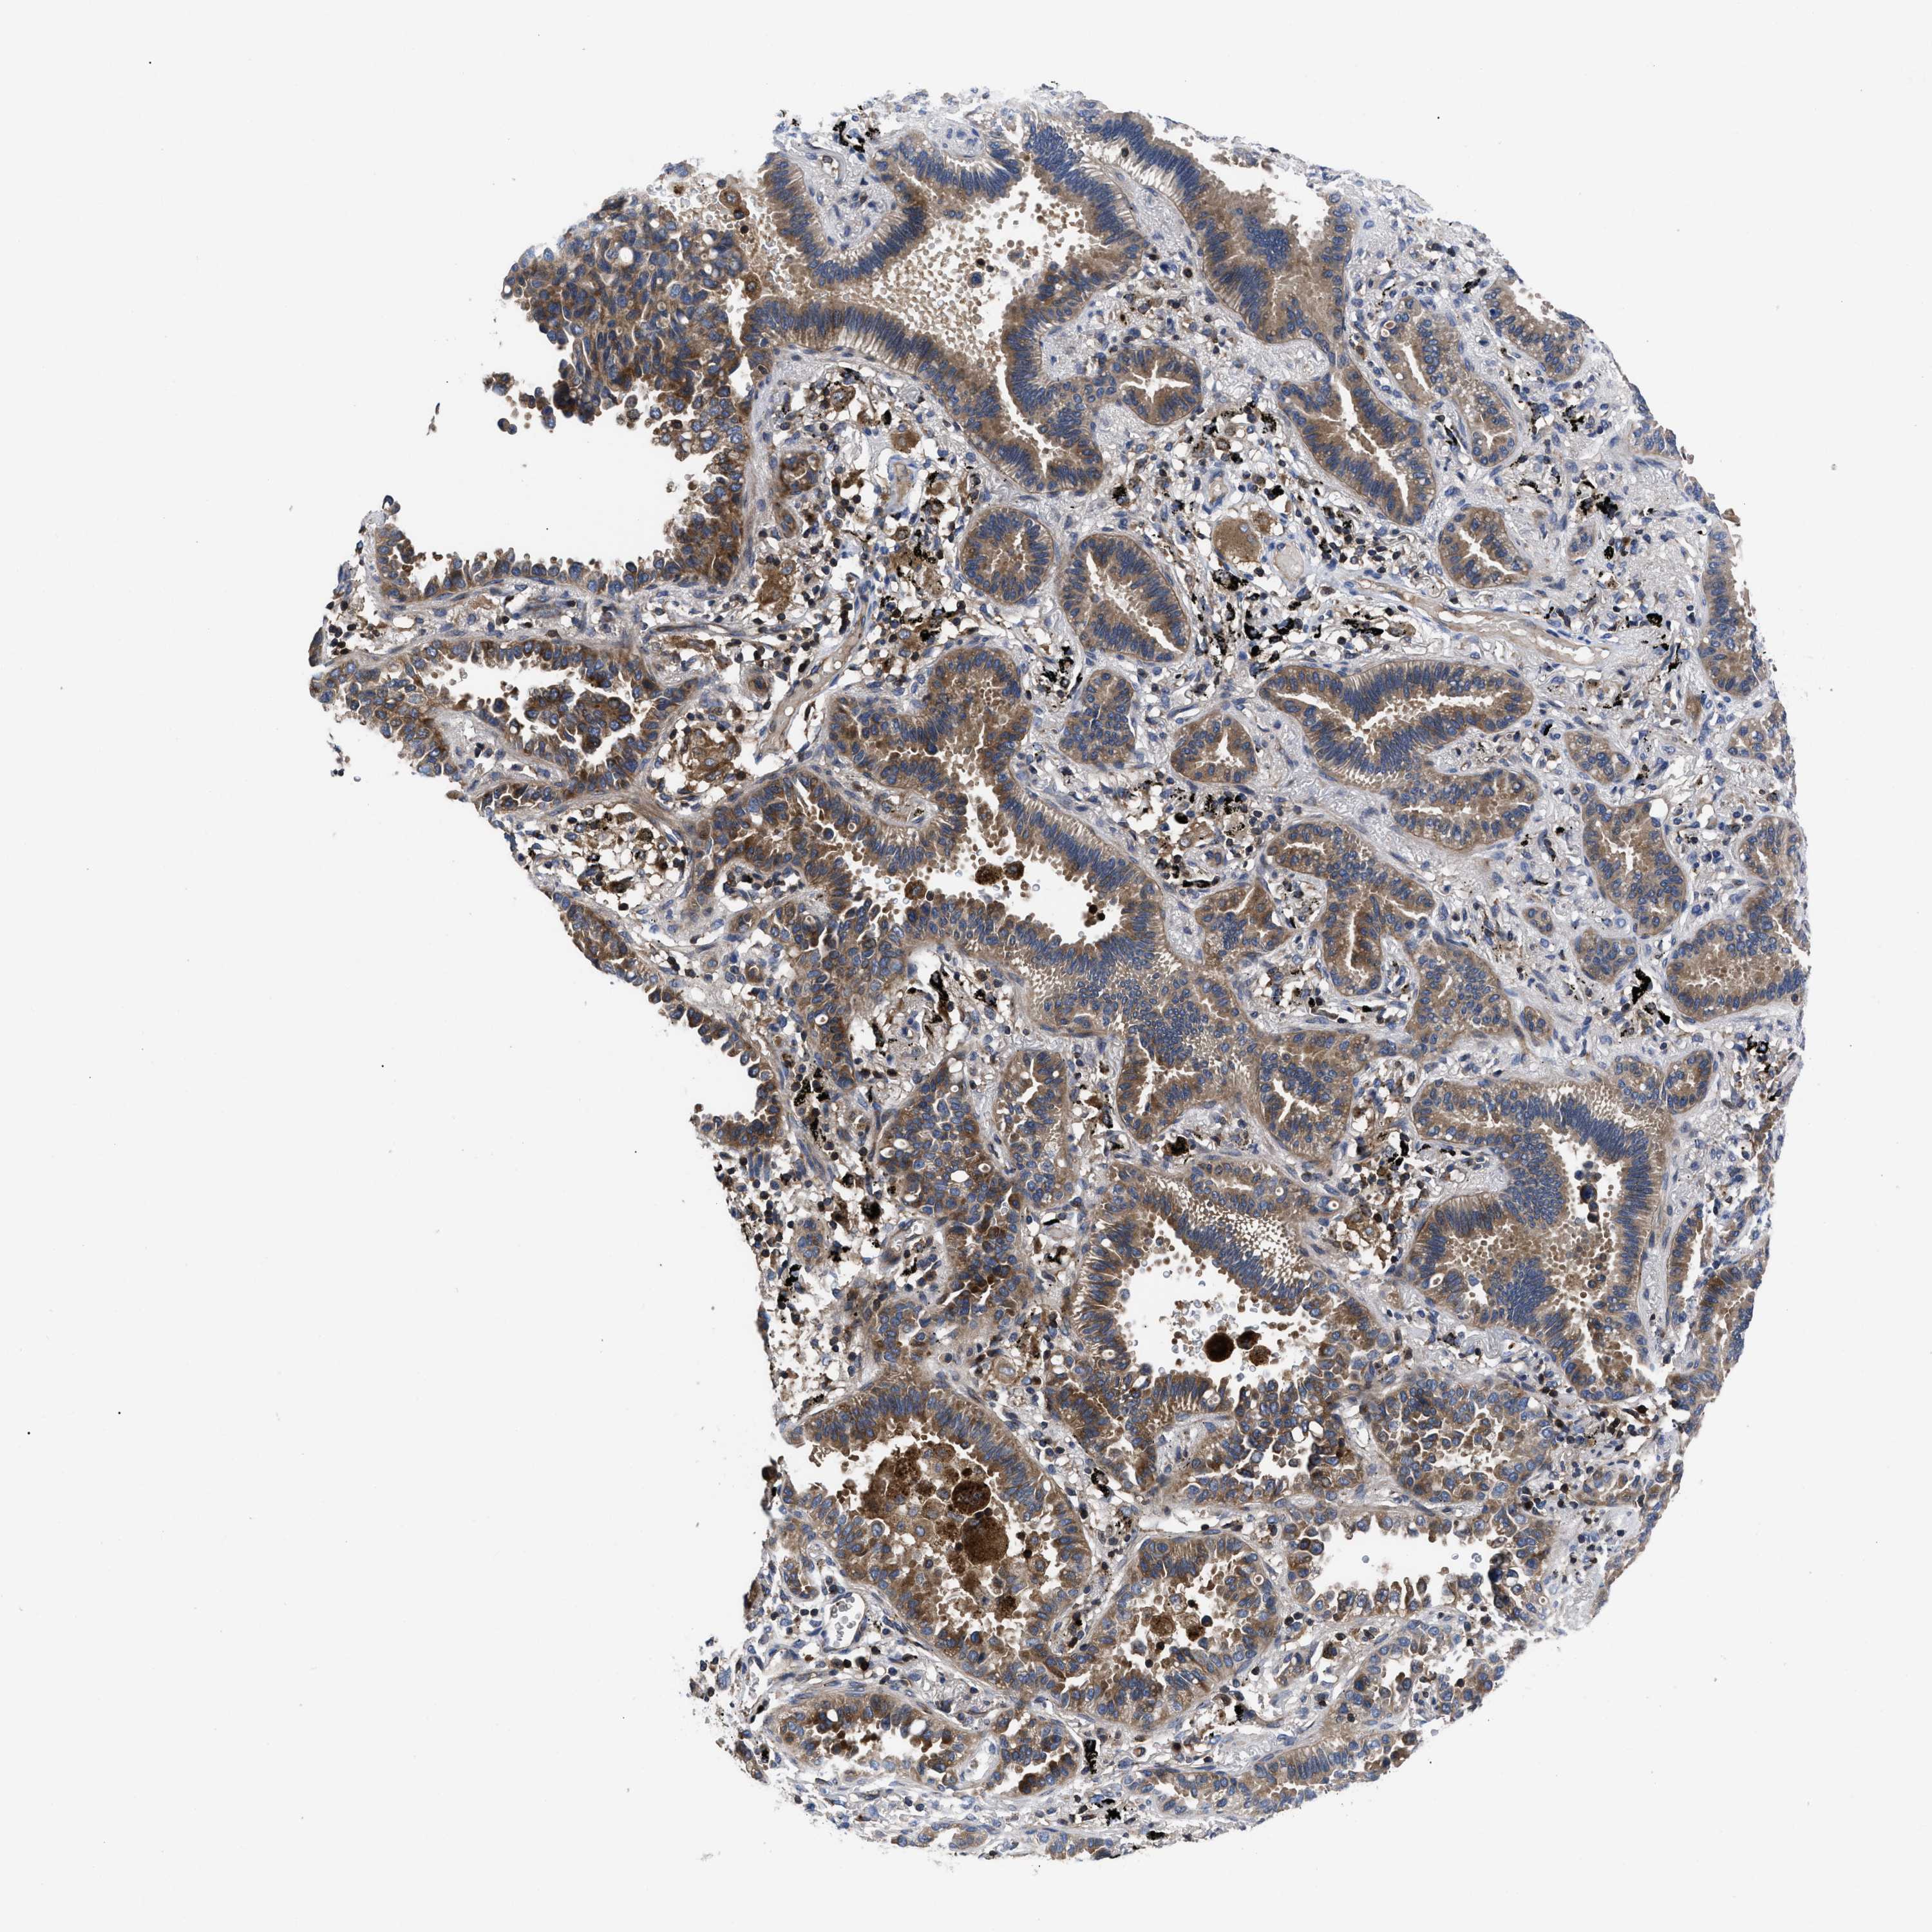

LUNG ADENOCARCINOMA (TCGA) - Interactive survival scatter ploti

The Survival Scatter plot shows the clinical status (i.e. dead or alive) for all individuals in the patient cohort, based on the same data that underlies the corresponding Kaplan-Meier plots. Patients that are alive at last time for follow-up are shown in blue and patients who have died during the study are shown in red.

The x-axis shows the expression levels (FPKM) of the investigated gene in the tumor tissue at the time of diagnosis. The y-axis shows the follow-up time after diagnosis (years). Both axes are complimented with kernel density curves demonstrating the data density over the axes. The top density plot shows the expression levels (FPKM) distribution among dead (red) and alive patients (blue). The right density plot shows the data density of the survived years of dead patients with high and low expression levels respectively, stratified using the cutoff indicated by the vertical dashed line through the Survival Scatter plot. This cutoff is automatically defined based on the FPKM cutoff that minimizes the p-score. The cutoff can be changed by dragging the vertical line or by entering a cutoff value in the square labeled "Current cut-off".

Under the Survival Scatter plot the p-score landscape (black curve; left axis) is shown together with dead median separation (red curve; right axis). Dead median separation is the difference in median mRNA expression between patients who have died with high and low expression, respectively. It is calculated as follows: median FPKM expression of dead patients with high expression - median FPKM expression of dead patients with low expression. This is intended to aid the user in visually exploring custom cutoffs and the associated p-scores and dead median separation.

Individual patient data is displayed and can be filtered by clicking on one or more of the category buttons on the top of the page. Categories describing expression level and patient information include: high, low, alive, dead, female, male and tumor stages. The scale of the x-axis can be toggled between linear and log-scale by clicking on the "x log" button. Mouse-over function shows TCGA ID, patient information and mRNA expression (FPKM) for each patient.

& Survival analysisi

Kaplan-Meier plots summarize results from analysis of correlation between mRNA expression level and patient survival. Patients were divided based on level of expression into one of the two groups "low" (under cut off) or "high" (over cut off). X-axis shows time for survival (years) and y-axis shows the probability of survival, where 1.0 corresponds to 100 percent.

YBEY is not prognostic in Lung Adenocarcinoma (TCGA)

Best expression cut offi

Based on the FPKM value of each gene, patients were classified into two groups and association between prognosis (survival) and gene expression (FPKM) was examined. The best expression cut-off refers the FPKM value that yields maximal difference with regard to survival between the two groups at the lowest log-rank P-value. Best expression cut-off was selected based on survival analysis .

When clicking on this number, the vertical dashed line indicating cut-off, the interactive survival plot, and the Kaplan-Meier curve will be adjusted to show results based on the best expression cut-off.

: 17.99

P scorei

Log-rank P value for Kaplan-Meier plot showing results from analysis of correlation between mRNA expression level and patient survival.

N/A

TCGA RNA samplesi

RNA-seq data is reported as average FPKM (number Fragments Per Kilobase of exon per Million reads), generated by the The Cancer Genome Atlas (TCGA) .

Normal distribution across the dataset is visualized with box plots, shown as median and 25th and 75th percentiles. Points are displayed as outliers if they are above or below 1.5 times the interquartile range. FPKM values of the individual samples are presented next to the box plot.

Average pTPM 19.5

Number of samples 497